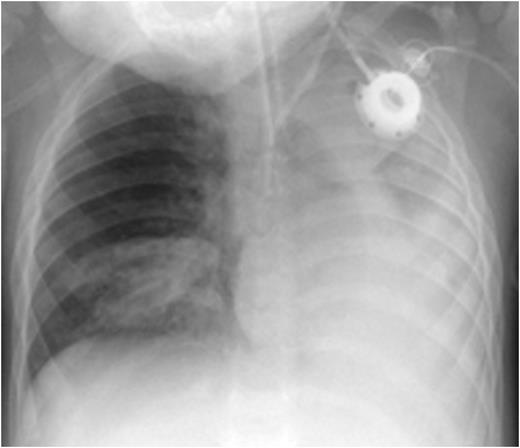

At 2 months of age he suffered a severe respiratory syncytial virus (RSV) infection requiring ventilatory support for 5 days and a 1 month hospitalization. From this time he had recurrent respiratory problems. From 4 months of age he was treated with fresh frozen plasma (FFP) 20 mL/kg/week. At 18 months of age he was found to have exophytic lesions within both the right and left main bronchi. He had one incident of acute severe dyspnea with cyanosis which responded to non- invasive oxygen insufflation. Subsequently he had repeated bronchoscopies with laser removal of bronchial lesions with FFP cover. At 20 months of age during preparation for bronchoscopy he had an episode of acute cyanosis and cardiac arrest with asystole and was resuscitated after 30 minutes. CXR showed atelectasis of the left lung and of the right lower lobe. He was admitted to the ICU and required both ventilatory and circulatory support. Profuse viscous lung secretions were aspirated.

CXR before administration of plasminogen showed atelectasis of the left lung and of the right lower lobe (left panel). Six weeks after initiation of regulalar plasminogen substitution ventilation in both lungs had improved significantly (right panel)